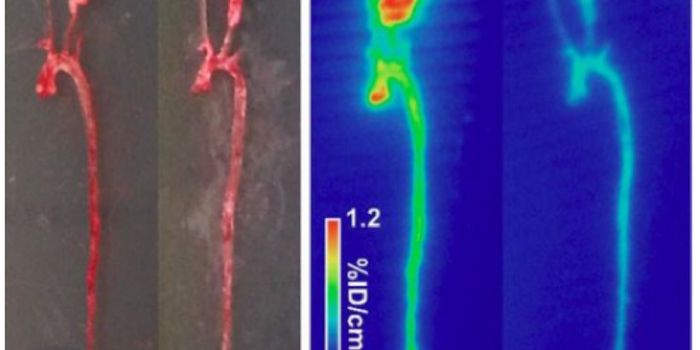

AUG 15, 2017Chemistry & PhysicsA common vascular disorder among male at or over 50, abdominal aortic aneurysm (AAA) is a localized blood filled bulge o ...